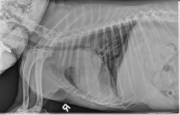

Today’s case is a 13-year-old Fox terrier with increased respiratory rate on excitement or in lateral recumbency. What are your findings?

On both lateral projections, there is increased soft tissue opacity in the cranial thorax, cranial to the hilus of the lungs and projecting dorsal to it on the left lateral projection. On the dorsoventral projection, the mass is located more in the left hemithorax and displaces the trachea to the right. The vasculature to the cranial lung lobes appears small, and the left caudal lobar arteries and veins are less visible than the right. In the portion of the abdomen included, the liver is enlarged. There is a diffuse bronchointerstitial pattern throughout the lungs. In the portion of the abdomen included, the liver is enlarged.

Differential diagnoses for the origin of the thoracic mass include the left cranial lung lobe, the mediastinum, or less likely the thoracic wall. The central location of the mass on both lateral projections suggests a dorsal mediastinal origin, however this should be confirmed with thoracic ultrasonography or echocardiography. The location is less typical of a ventral mediastinal mass such as thymoma. The small pulmonary vessels may suggest compression of the pulmonary artery by the mass. The diffuse bronchointerstitial pattern may be inflammatory or fibrotic in nature.

Thoracic ultrasonography and echocardiography were performed and the mass was seen to originate in the region of the aortic arch and surrounded the main pulmonary artery. A fine needle aspirate was non-diagnostic. Differential diagnoses included chemodectoma and ectopic thyroid carcinoma.